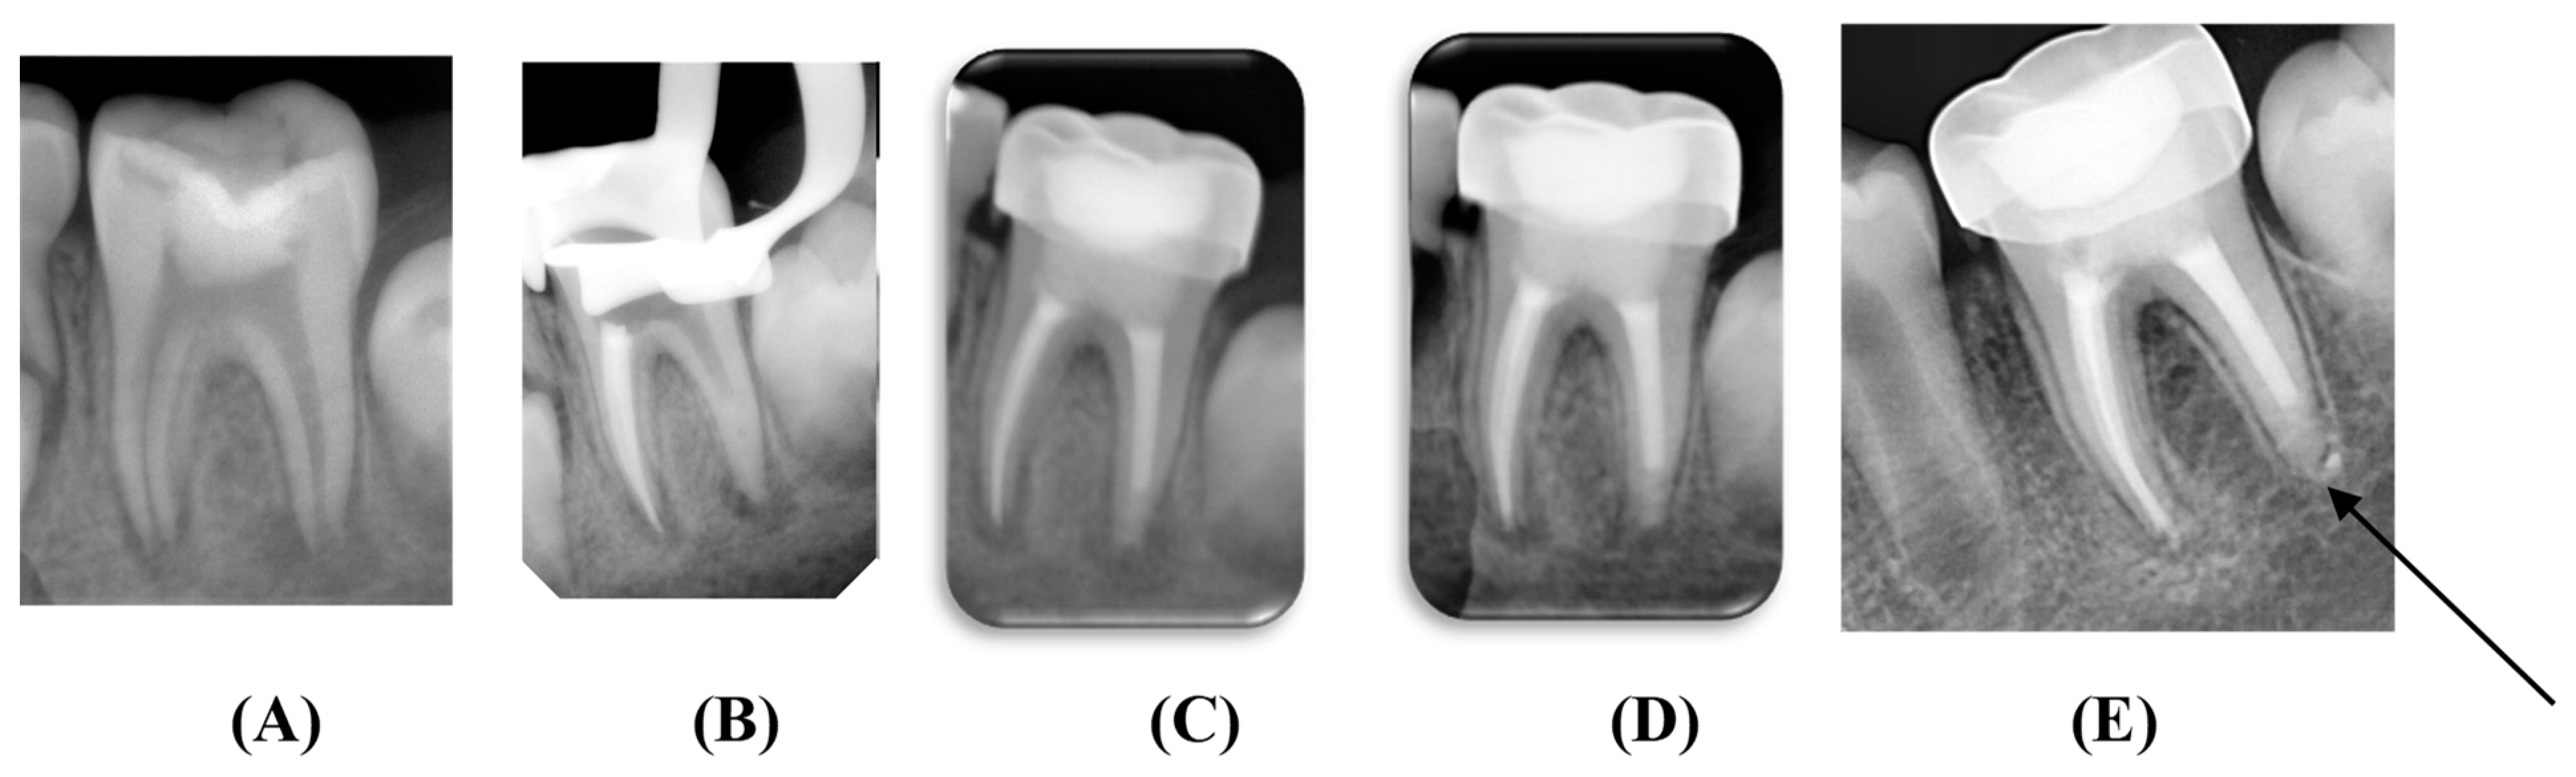

2.7. Clinical Procedures

2.9. Filling of the Root Canals

2.10. Coronal Restoration

2.11. Clinical and Radiographic Evaluations